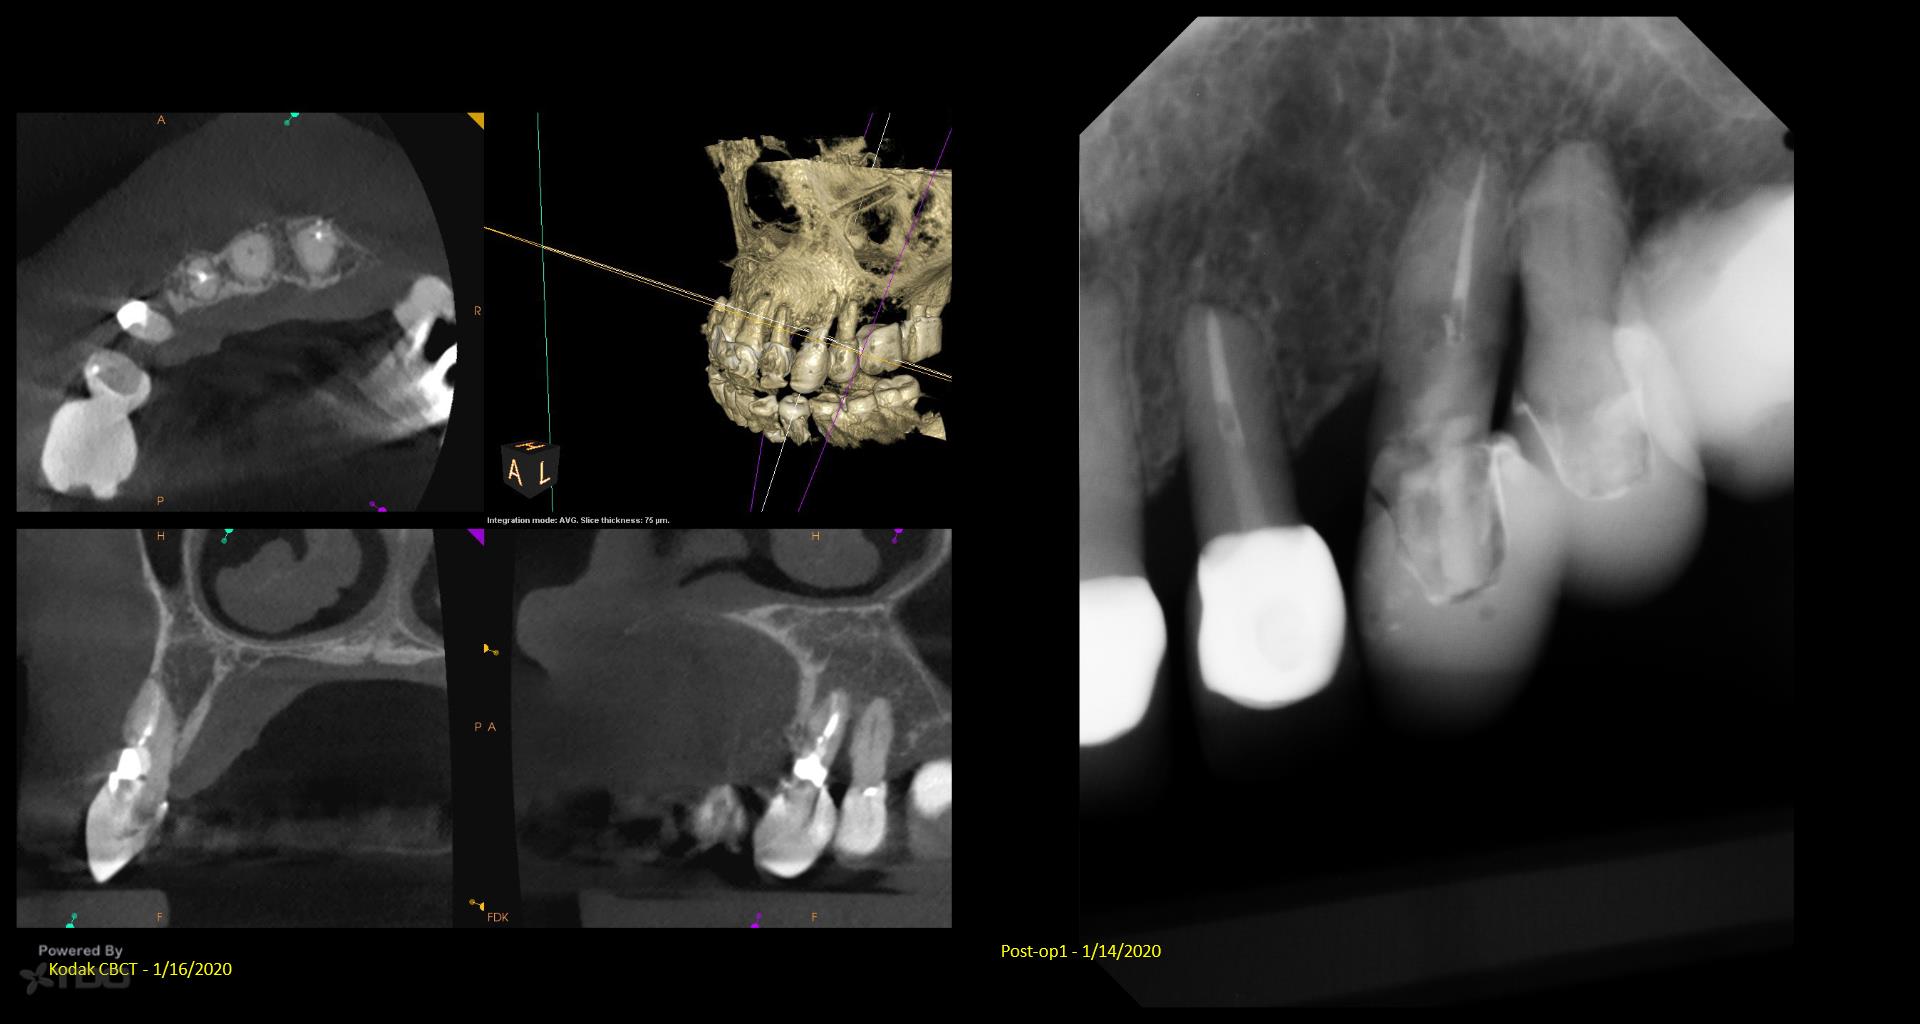

I posted this last month after the consult. There was mixed TDO advice—some said “do it” and others said monitor. Reluctantly, I did it Monday. I couldn’t really address the ECIR that was sub-osseous without removing way too much bone. I just hit it with the Pear Diamond as well as I could. Time will tell if it was a fool’s errand. I video’d the whole thing but don’t have the time to edit it. gbc